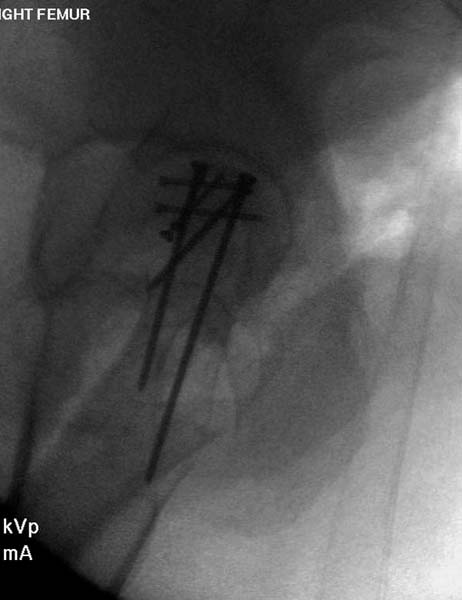

> стабильная.. На третьий день провели стабилизацию перелома бедра

> антеградным остеосинтезом.

> Для решения проблемы дистальной блокировки компания DigiMed недавно

> предложила систему блокировки без рентгена. Пока в стране только два набора

> и только для антеградных гвоздей, но компания работает над созданием

> устроиства для других гвоздей тоже..

> Результат первых случаев показала отсутствие разницы между занятиями на

> муляжах, а также Workshop и с удивительной точностью вывел латерально над

> кожей специальное сверло. Дальше по сверлу тонкий направитель и проводится

> сверление каннюлированным сверлом....